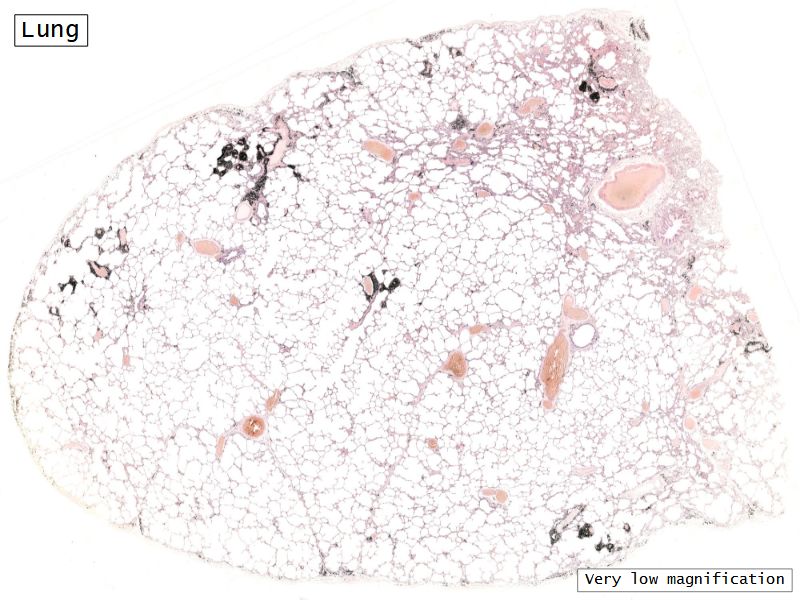

Fill in all the missing labels, and assess as you move through the slides. Answers on the down slide. It is important to do this using pen and paper, and not just glance through the images.